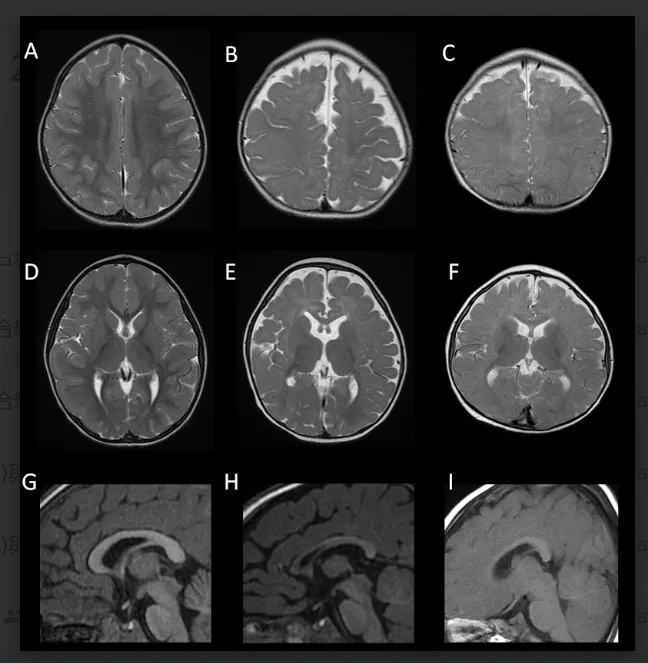

FOXG1症候群的腦部磁振造影。(陽明交大提供)

陽明交大腦科學研究所蔡金吾特聘教授與台大兒童醫院院長李旺祚醫師,分析來自歐洲、北美、日本與台灣等國共14名FOXG1症候群患者的臨床症狀與腦部影像資料,建立一項結合實驗室功能檢測的創新流程,包含蛋白表現分析、基因調控測試與小鼠胚胎細胞遷移實驗3種方式,成功預測超過9成病患腦部異常的嚴重程度。這項突破刊登在國際權威期刊《Molecular Psychiatry》(分子精神醫學)。